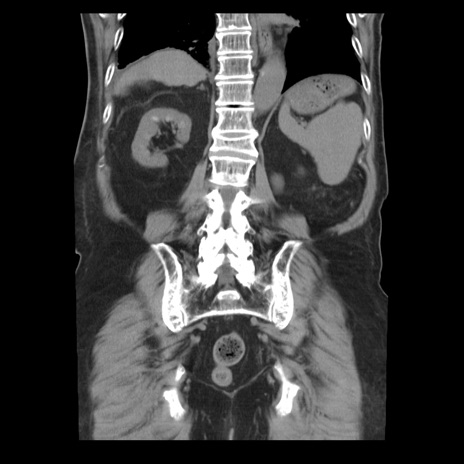

症例21(冠状断像)

【症例】70歳代男性

【主訴】腹痛

【現病歴】肝硬変・肝細胞癌にてかかりつけの方。約9時間前に食後より腹痛出現。症状が徐々に増悪し、嘔吐出現したため来院。

【既往歴】肝硬変、肝細胞癌(RFA、TACE後)

【身体所見】意識清明、表情苦悶様、BT 36℃、BP 129/78mmHg、P 88bpm、SpO2 97%(RA)、右上腹部から心窩部にかけて圧痛あり、反跳痛なし、筋性防御あり。

【データ】WBC 5800、CRP 0.16